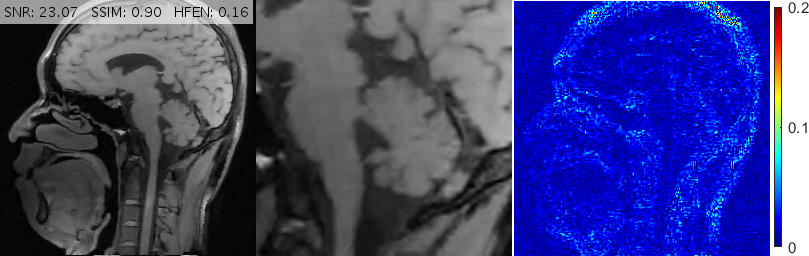

Fig. 6 depicts the reconstruction results for above setups. As attested by the magnified views and error metrics inserted to the top of each reconstruction, TV and TGV significantly degrade the reconstructed image in the rotated setup while RITV gives a remarkably consistent and high-quality result which is hardly distinguishable from the upright solution (note that HFEN and SSIM indices do not change in RITV after rotation). Of course, the upright and rotated directions are only chosen relatively and can always be swapped, nevertheless, the point is TV and TGV fail in at least one of the orientations while RITV succeeds in both. Note that if the selected MR image and Cartesian mask are denoted by and respectively, then a simple machine-aided computation shows that . Therefore, even though the norm-preserving assumption of Theorem 2.1 does not hold true in this experiment (and in fact in many practical situations), the result of RITV is still incredibly isotropic.

Fig. 10 shows the performance of various algorithms for a sagittal head scan reconstruction under 16% spiral sampling. The solutions provided by pFISTA and TL miss much of the image content due to over-smoothing. TGV+Shearlet leaves many incoherent artifacts on all regions. The magnified views obviously show that BM3D degrades the image by leaving block artifacts around the cerebellum and streaking artifacts on the medulla and the visual cortex. DAMP, GBRWT, ADMM Net and FDLCP provide more accurate results, however, by inspecting the magnified views it becomes evident that some small artifacts are introduced in DAMP near the caudate nucleus and beneath the cerebellum while a dark hole at the center of the cerebellum has been almost entirely smoothed out by the other three methods. The proposed method (labeled ‘New’) accurately captures this hole and corrects all the errors mentioned above.

For convenience, in Figs. 10, 11 and 13 we have inserted the SNR, SSIM and HFEN values for each method to the top of the corresponding reconstructed image. Moreover, some reconstruction errors in compared methods and their corrections in the proposed method are annotated with arrows.